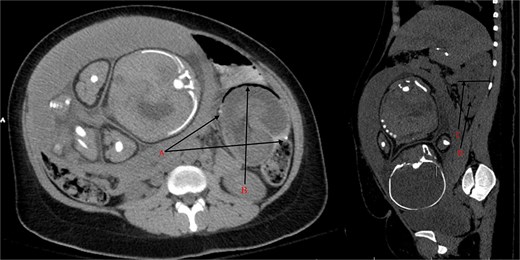

Transvaginal ultrasound showed no evidence of placental abruption and a viable fetus. Computed tomography (CT) scan of the abdomen/pelvis was concerning for intussusception in the LUQ at the jejunojejunostomy anastomosis, causing a small bowel obstruction and radiographic evidence of ischemia (Fig. 1). Patient was taken for an exploratory laparotomy and a concomitant cesarean section. Following an uneventful cesarean section, the LUQ was explored. A 20-cm dusky segment of the proximal common channel had telescoped retrogradely into the jejunojejunostomy anastomosis, causing a complete small bowel obstruction. The afferent and Roux limbs were dilated but viable. Following unsuccessful attempts at reducing the intussusception, the entire jejunojejunostomy anastomosis was resected and reconstructed.

(A) Staple line of the jejunojejunostomy anastomosis. (B) Pneumatosis intestinalis from the ischemic intussusceptum. (C) Cross-section of the intussuscipiens measuring up to 6.3 cm (n ≈ 3 cm). (D) Mesenteric vessels in the lumen on the intussucipiens.